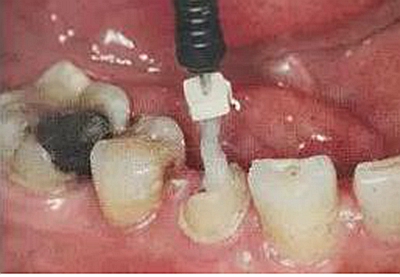

用P鉆從1號(hào)到4號(hào)逐級(jí)擴(kuò)大根管,如果根管是大錐度預(yù)備,可以省略1號(hào)。在預(yù)備之前要測(cè)量長(zhǎng)度,將最終預(yù)備的長(zhǎng)度用皮圈標(biāo)記在鉆針上。用1號(hào)P鉆時(shí)尤其要小心,是最容易斷的,用的時(shí)候要注意手法。

每個(gè)品牌的纖維樁都會(huì)有配套的鉆,在用P鉆預(yù)備后就應(yīng)該用廠家的鉆了,纖維樁預(yù)備時(shí)不用去除根管內(nèi)壁上的倒凹,只要保證足夠的長(zhǎng)度和直徑即可。

隨后還要用P鉆預(yù)備,將根管內(nèi)壁上完全清理干凈,殘留的任何一點(diǎn)東西者會(huì)影響粘接效果。